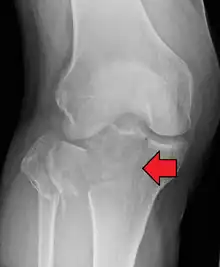

• Type IV = Medial tibial plateau fracture, with or without depression; may involve tibial spines; associated soft tissue injuries.

This is a medial tibial plateau fracture with a split or depressed component. It is usually the result of a high energy injury and involves a varus force with axial loading at the knee. Represent 10% of all tibial plateau fractures. There is high risk of damage to the popliteal artery and peroneal nerve and therefore carry a worse prognosis. May include distraction injuries to lateral collateral ligament, fibular dislocation/fracture, posterolateral corner.